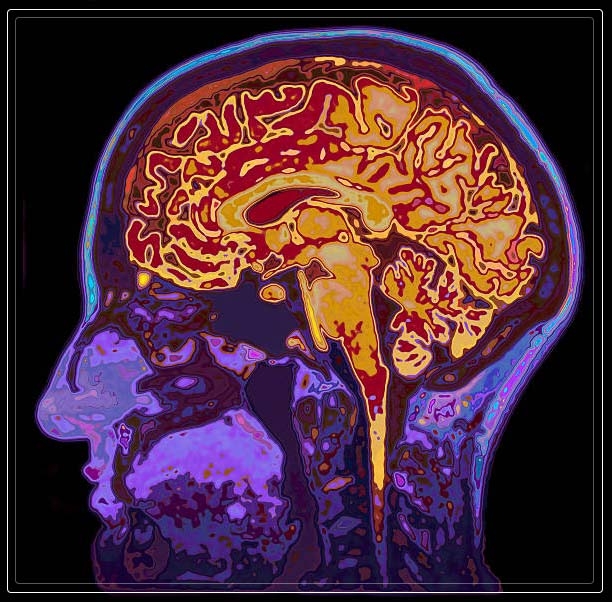

dementia